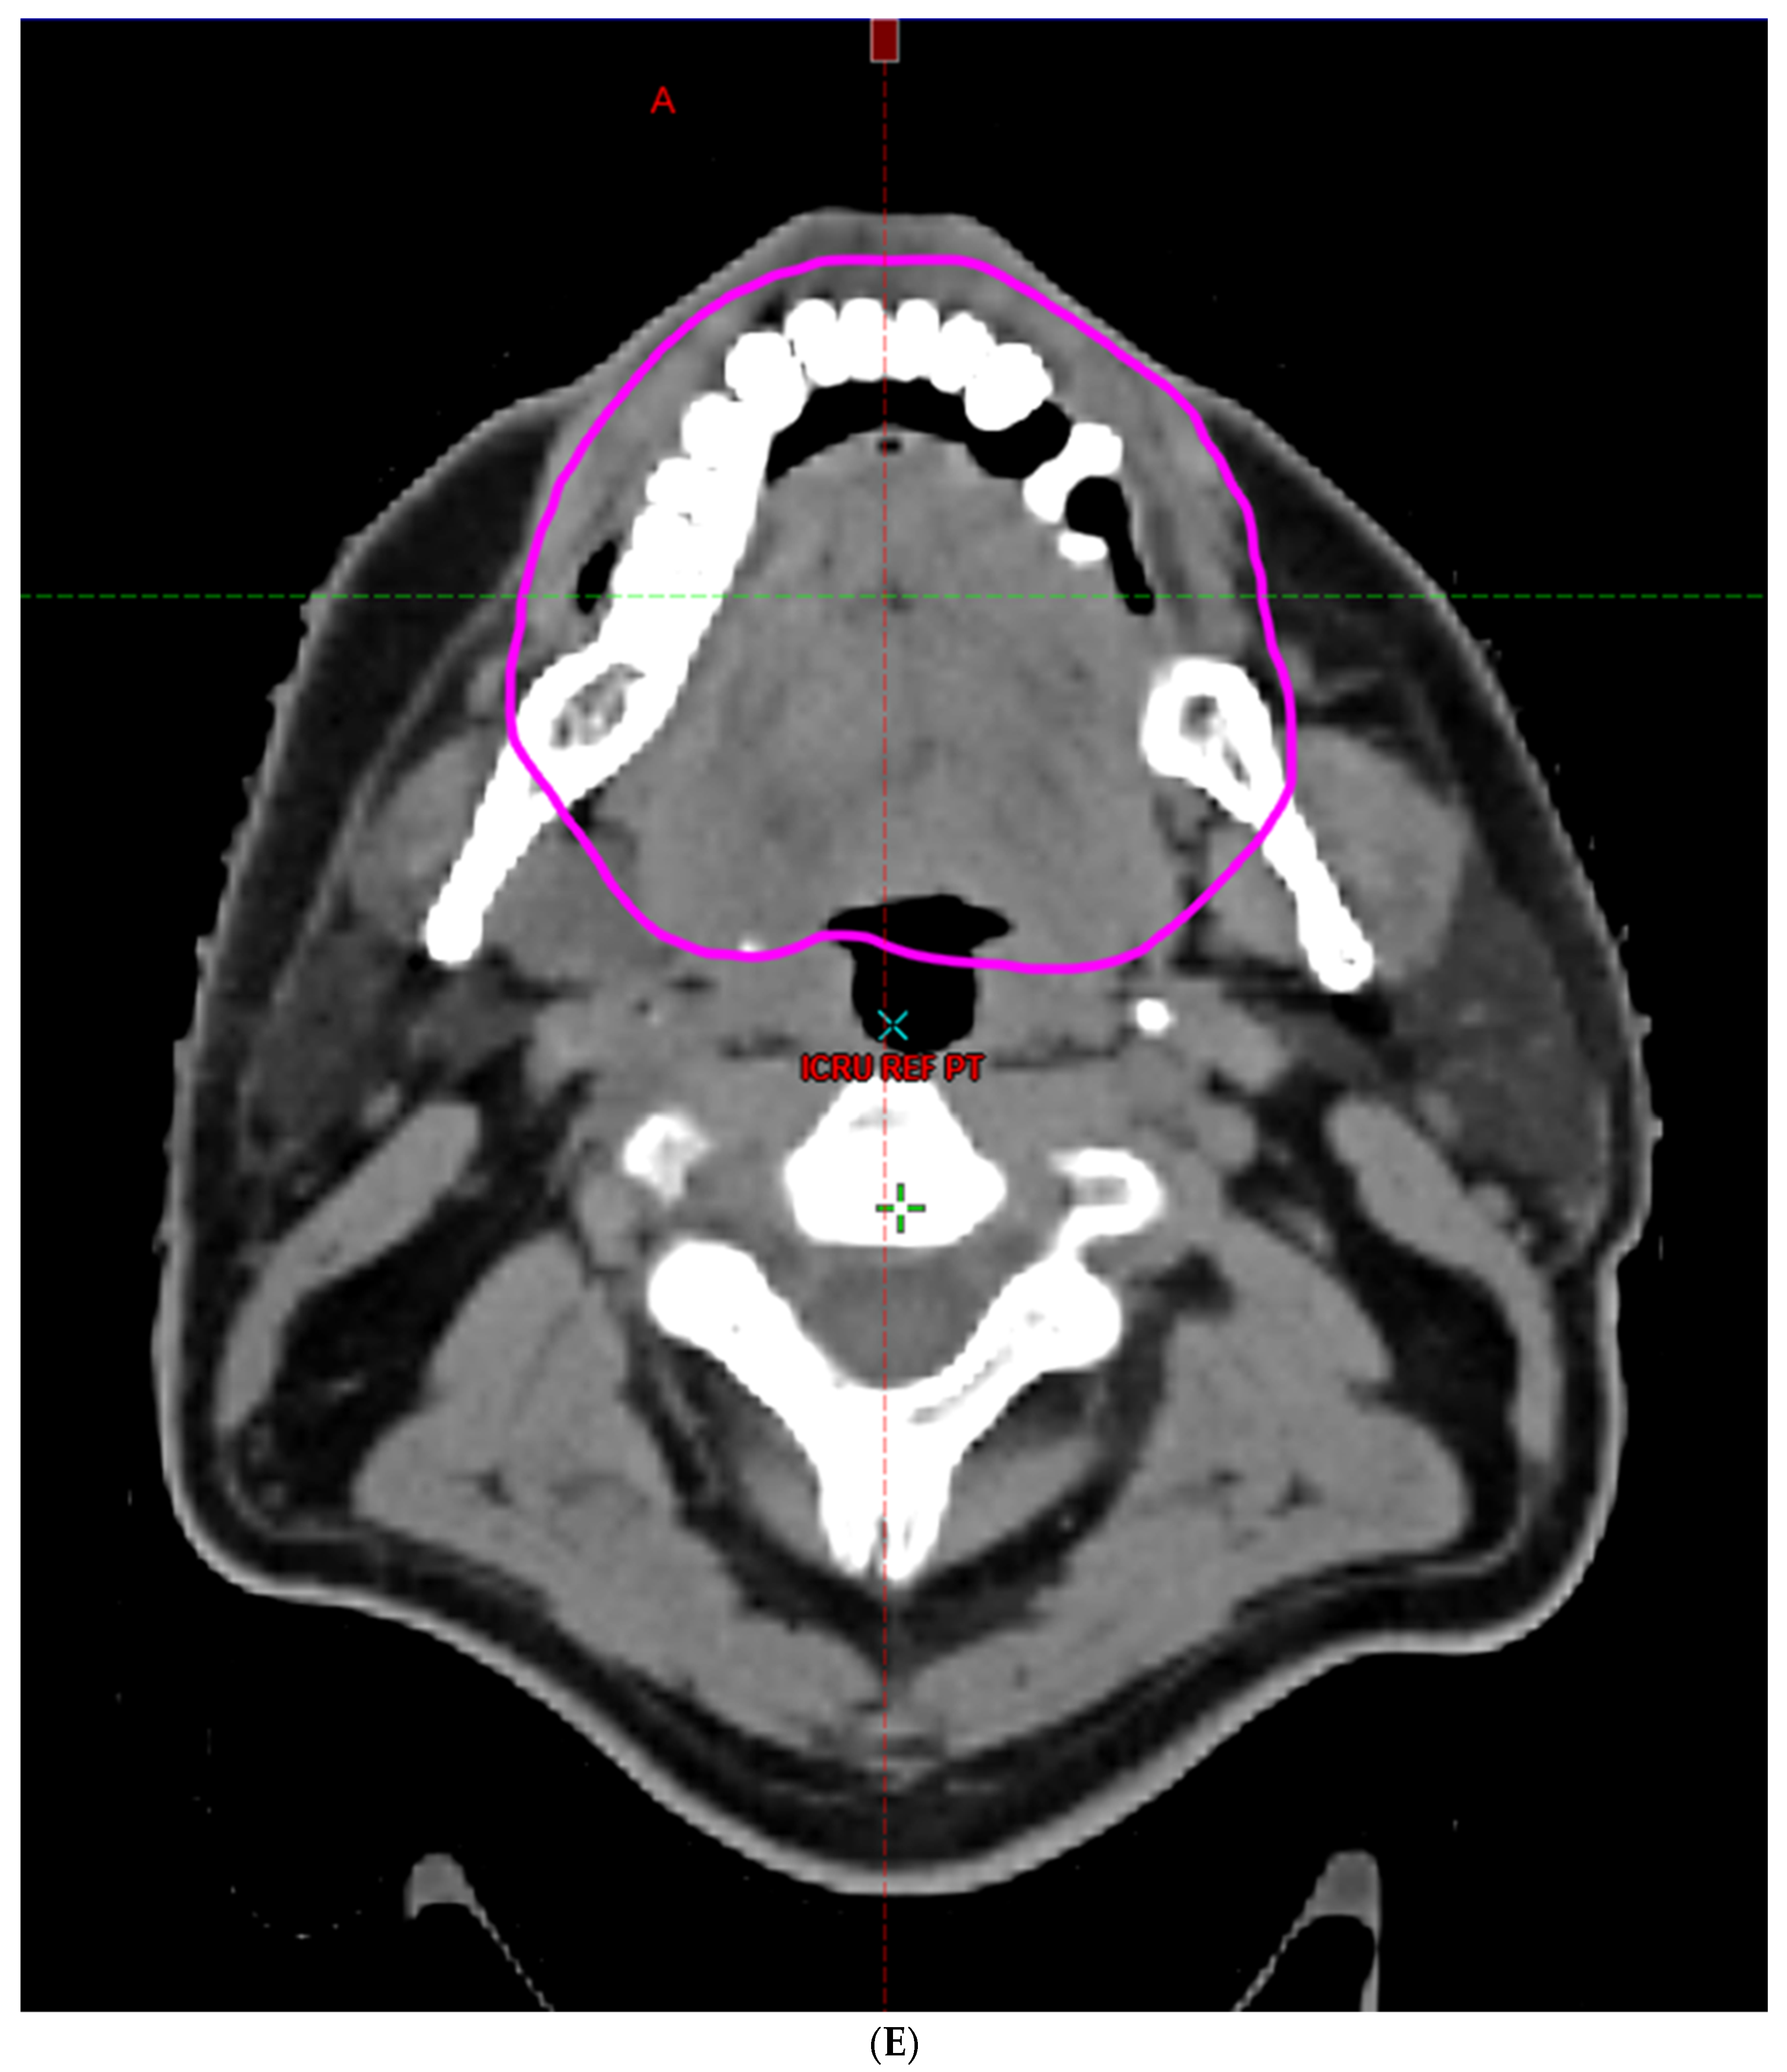

- Hoebers, F.; Yu, E.; Thorstad, W.; O’Sullivan, B.; Dawson, L.A.; Hope, A. A Pragmatic Contouring Guideline for Salivary Gland Structures in Head and Neck Radiation Oncology. The MOIST Target. Am. J. Clin. Oncol. 2013, 36, 70–76. [Google Scholar] [CrossRef]

- Brouwer, C.L.; Steenbakkers, R.J.; Bourhis, J.; Budach, W.; Grau, C.; Grégoire, V.; Van Herk, M.; Lee, A.; Maingon, P.; Nutting, C.; et al. CT-based delineation of organs at risk in the head and neck region: DAHANCA, EORTC, GORTEC, HKNPCSG, NCIC CTG, NCRI, NRG Oncology and TROG consensus guidelines. Radiother. Oncol. 2015, 117, 83–90. [Google Scholar] [CrossRef]

- Li, K.; Yang, L.; Hu, Q.-Y.; Chen, X.-Z.; Chen, M.; Chen, Y. Oral Mucosa Dose Parameters Predicting Grade ≥ 3 Acute Toxicity in Locally Advanced Nasopharyngeal Carcinoma Patients Treated with Concurrent Intensity-Modulated Radiation Therapy and Chemotherapy: An Independent Validation Study Comparing Oral Cavity versus Mucosal Surface Contouring Techniques. Transl. Oncol. 2017, 10, 752–759. [Google Scholar] [CrossRef]

- Sun, Y.; Yu, X.-L.; Luo, W.; Lee, A.W.; Wee, J.T.S.; Lee, N.; Zhou, G.-Q.; Tang, L.-L.; Tao, C.-J.; Guo, R.; et al. Recommendation for a contouring method and atlas of organs at risk in nasopharyngeal carcinoma patients receiving intensity-modulated radiotherapy. Radiother. Oncol. 2014, 110, 390–397. [Google Scholar] [CrossRef]

- Dean, J.A.; Welsh, L.C.; Gulliford, S.L.; Harrington, K.J.; Nutting, C.M. A novel method for delineation of oral mucosa for radiotherapy dose–response studies. Radiother. Oncol. 2015, 115, 63–66. [Google Scholar] [CrossRef]